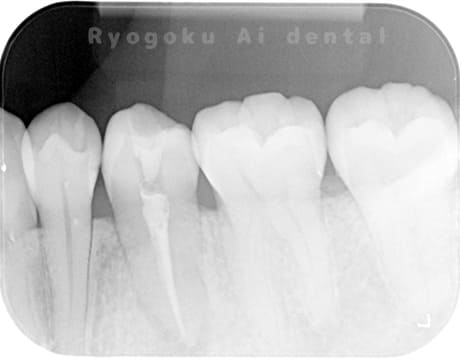

Case01

-

根管内の異物

- 原因

- 根管内異物(ファイル破折)による慢性根尖性歯周炎

- 治療期間

- 3ヶ月

- 治療内容

- マイクロスコープを使用した根管内異物除去並びにマイクロエンド

- 治療費用

- 121,000円(ファイル除去費用も込み)

他院で細い器具(ファイル)が根管内に破折した状態で、咬合痛を主訴に来院された患者様です。ファイルをマイクロスコープ下で除去し、根管治療を行ないました。